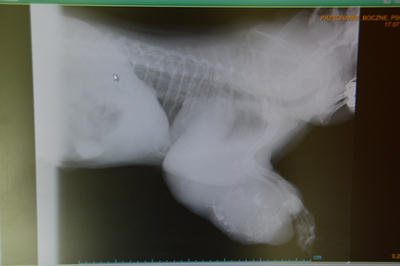

Zmiana rozrostowa dotycząca tkanek miękkich na przedniej kończynie.